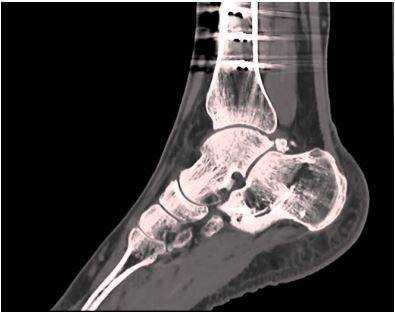

Томограмма голеностопного сустава

Травмы и различные повреждения голеностопа требуют незамедлительного обследования. Голеностопный сустав наряду со своей хрупкостью несёт колоссальные нагрузки и часто подвергается повреждениям разной степени выраженности. Своевременность выявления и анализа разрушений во многом определяет дальнейшую успешность лечения и восстановления нарушенной функции. Перед тем как принять лечебные меры, необходимо детально понять и проанализировать возникшую проблему. С этой целью современной медициной активно и успешно используется компьютерная томография голеностопного сустава.